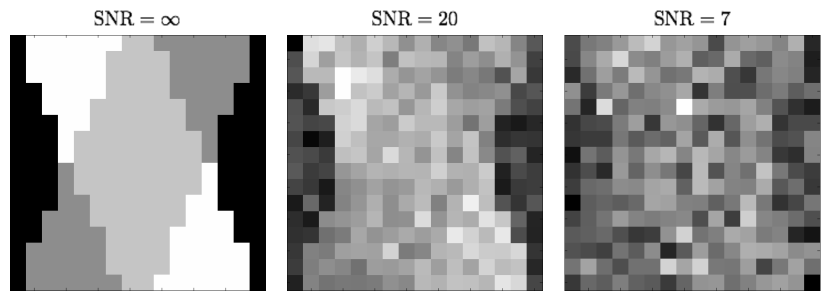

The data simulation was repeated for two different values of , viz. s/mm2 and s/mm2, with the corresponding SNRs of Rician noise444In the case at hand, SNR was defined to be a ratio of the mean amplitude of a noise-free HARDI signal to the standard deviation of the Gaussian noise contaminating the complex MR readout. being 20 and 7. It should be noted that the above choice of -values and their related SNRs is by no means arbitrary, but intended to imitate a real-life situation, in which increasing the value of comes at the price of a substantially reduced SNR. (The effect of Rician noise is exemplified in Fig. 3 where a noise-free “axial slice” of the simulated HARDI signal (left) is shown along with its noise contaminated versions for SNR = 20 (middle) and SNR=7 (right).) In such a case, the adverse effect of measurement noises could effectively counterpoise the gain in signal bandwidth which comes with exploiting higher -values. In the context of SD, it is therefore important to understand the trade-off between the values of and SNR under various regularization schemes.